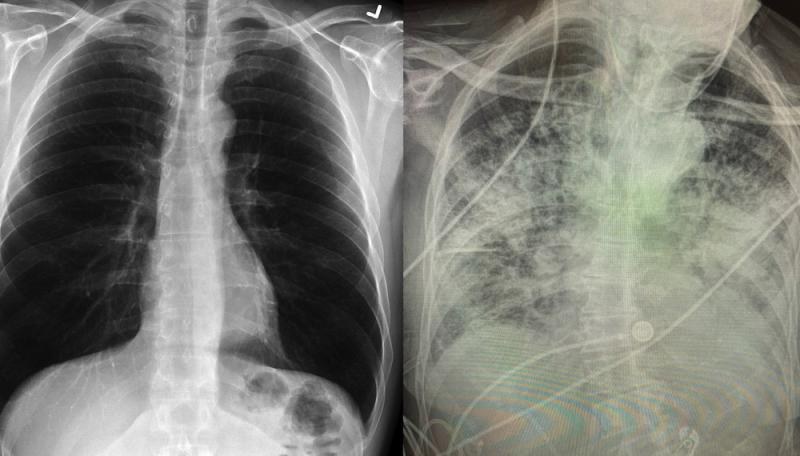

De acuerdo a una doctora de Texas, los pulmones después de sufrir la enfermedad de la COVID-19 pueden presentar un daño severo, incluso en casos asintómaticos, incluso peor que en casos de fumadores.